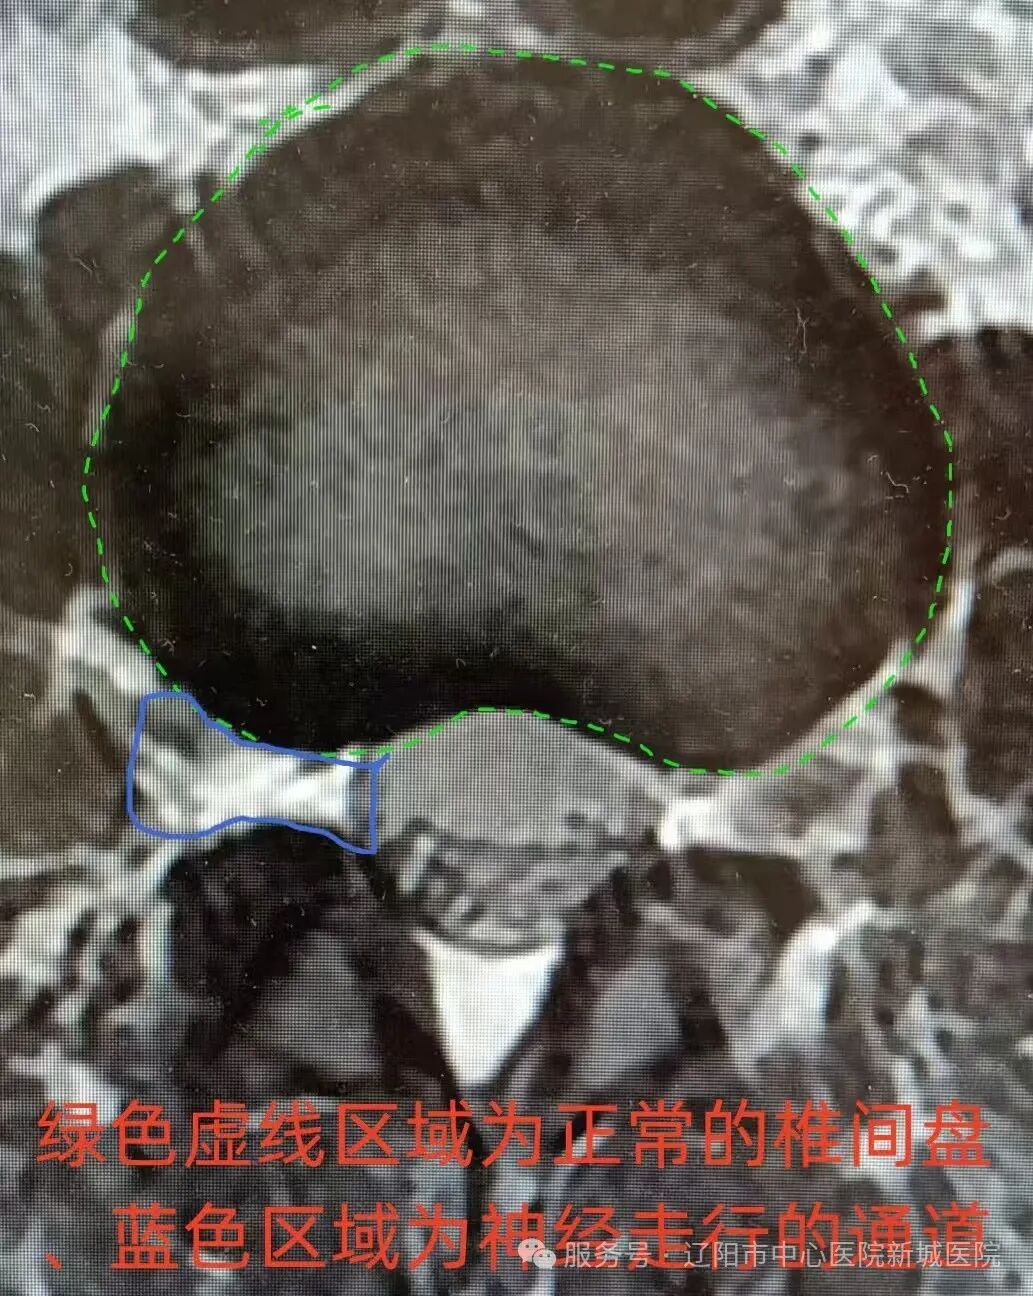

康復(fù)科副主任王松山接診后,經(jīng)過詳細(xì)查體和影像檢查,周女士被診斷為腰椎間盤突出,伴側(cè)隱窩及椎管狹窄,腰間盤突出巨大,具有典型的手術(shù)指征。